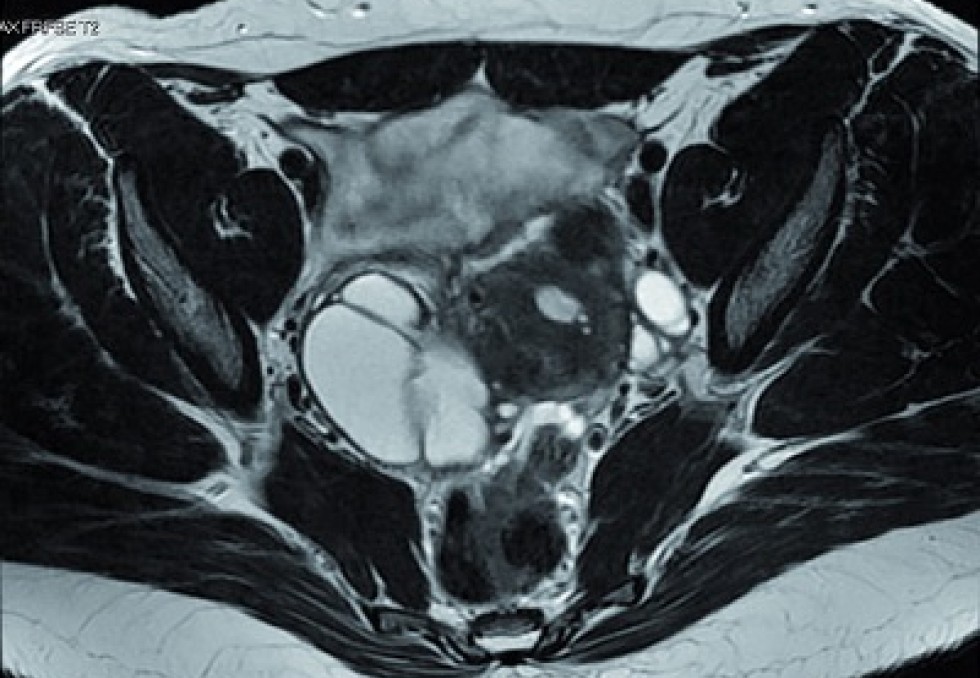

L’endométriose se caractérise par la présence anormale de tissus semblables à la muqueuse utérine en dehors de l’utérus, provoquant inflammation, lésions, douleurs et, dans un tiers des cas, infertilité. Les mécanismes sont mal connus. L’hypothèse principale est celle des menstruations rétrogrades : du sang remonte par les trompes de Fallope, et des cellules d’endomètre ainsi transportées peuvent s’implanter dans la cavité abdominale. Cependant, ce reflux concernerait 90 % des femmes alors que seules 10 % développent des lésions. « Dans l’endométriose, les cellules échappent à la surveillance du système immunitaire. Ont-elles des particularités faisant que le système immunitaire ne les reconnaît pas, ou bien celui-ci n’a pas de raison d’attaquer ces cellules vivantes et en bonne santé ?, interroge Ludivine Doridot, maîtresse de conférences à l’Université Paris Cité, Chaire Inserm, Institut Cochin. Ce phénomène pourrait s’expliquer par la quantité de sang, car les femmes ayant une endométriose ont des pertes plus importantes… »